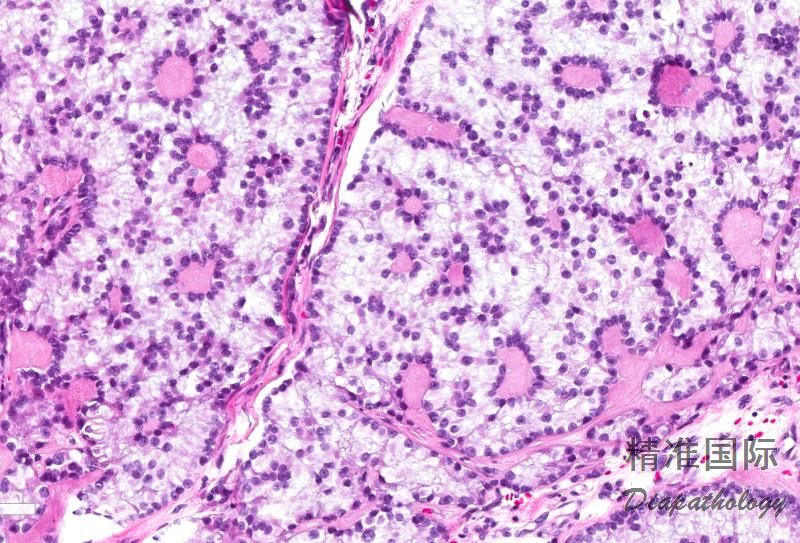

基本特点是由单一散在分布或结节状聚集的简单或复杂的环状小管结构组成;

简单型小管呈环形,细胞核位于外周,围绕中央基底膜样物质构成的透明小体,其间是无核的胞质区,构成环形结构的主要部分,无管腔;

复杂型环形小管数量更多,都是圆形结构,由相通的环形结构围绕着多个透明小体而构成;

有些病例中含有局灶伸长的管状结构,呈 Sertoli 细胞瘤分化,而另一些病例局灶含有 Call-Exner 小体,呈粒层细胞瘤分化;

间质为纤维性伴玻璃样变性,围绕细胞巢,并与细胞巢中央的透明小体连通;